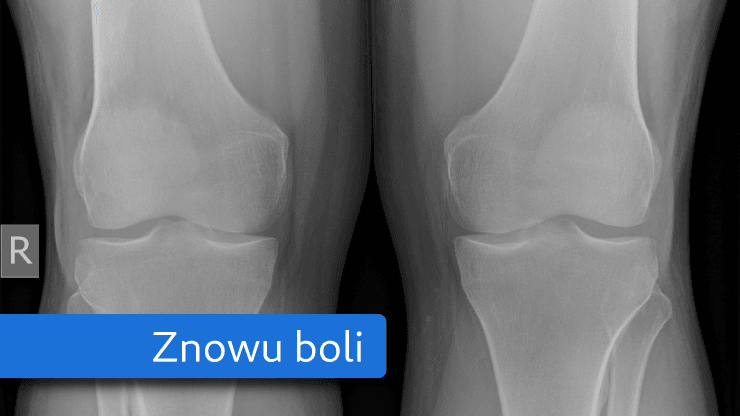

Platelet-rich Plasma says no to surgery or medication; however, the treatment still gives a natural and safe look. A tiny amount of the patient’s blood is drawn, usually from their arm. After that, the blood sample is spun around to separate each component, isolating the growth factors and platelets from the other blood components.